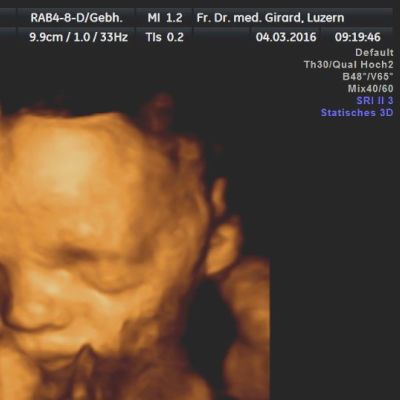

Der Ultraschall hilft uns dabei als einzige Methode, das ungeborene Kind in der Gebärmutter direkt sichtbar zu machen.

können wir die Intaktheit und das Alter der Schwangerschaft feststellen. Diese Information ist von grosser Bedeutung, um beispielsweise in der Spät-Schwangerschaft ein allfälliges vermindertes Wachstum des Kindes erkennen zu können. Auch können Mehrlinge mit hoher Sicherheit erfasst oder ausgeschlossen werden. Zudem kann schon in diesem frühen Alter eine Reihe schwerer Fehlbildungen erkannt werden. Mit der Messung der Nackenhaut-Dicke können Hinweise auf eine mögliche Chromosomen-Störung (beispielsweise das Down-Syndrom = Trisomie 21) erfasst werden.